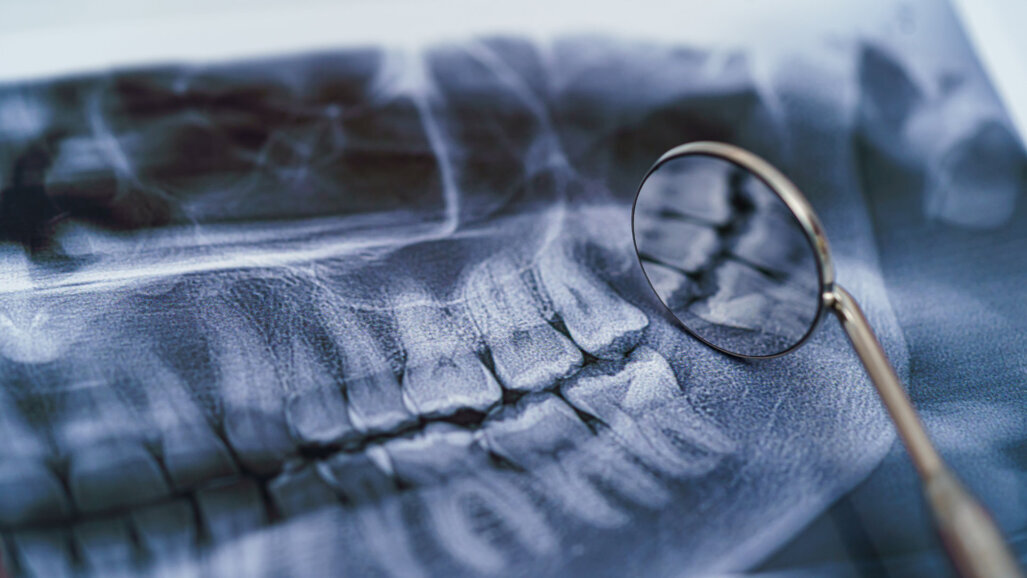

Gegenstand des jüngsten Forschungsprojektes von Barbara Kirnbauer war die digitale Volumentomographie, mit der es gelingt, dreidimensionale Röntgendatensätze der Kiefer und angrenzenden Strukturen zu erstellen. Konkret ging es darum, wie gut ein neu entwickeltes künstliches neuronales Netzwerk krankhafte Veränderungen im Kieferknochen rund um die Wurzelspitze erkennen kann. Die Interpretation der Röntgendatensätze ist zeitaufwendig, verlangt viel Expertise und kann bei Fehlern gravierende Folgen für die Gesundheit der Patient*innen nicht nur im Kieferbereich haben. Man weiß bereits, dass der Einsatz von künstlicher Intelligenz das Potenzial hat, Fehlerquellen zu reduzieren, die Sicherheit zu erhöhen und zeitliche Ressourcen von Mediziner*innen zu schonen.

Gesucht wurden in den Datensätzen sogenannte periapikale osteolytische Läsionen. Periapikal bezeichnet etwas an oder rund um die Zahnwurzel, osteolytisch bedeutet den Knochen auflösend und eine Läsion ist eine krankhafte Veränderung des Gewebes – in diesem Fall verursacht durch eine bakterielle Infektion mit Eintrittspforte an der Zahnkrone. Unbehandelt können diese entzündlichen Läsionen zu Problemen wie Zahnschmerzen, Abszessen oder Zahnverlust führen. Nicht nur im Kieferbereich, sondern auch im ganzen Körper kann es infolge eines Zahnherdes zu krankhaften Veränderungen kommen, indem sich die verursachenden Bakterien über die Blutbahn ausbreiten. Daher ist das schnelle, präzise und verlässliche Erkennen der zum Teil wenige Millimeter kleinen Veränderungen besonders wichtig.

Erprobt wurde das entwickelte KI-System in dieser Studie an insgesamt 144 dreidimensionalen Datensätzen mit insgesamt 2.128 Zähnen. So konnte die Studie für das recht frühe Stadium der Forschung in diesem Bereich bereits eine durchaus beeindruckende Anzahl an untersuchten Studienobjekten vorweisen. Darüber hinaus lieferte das programmierte neuronale Netzwerk auch äußerst vielversprechende Ergebnisse, die hochrangig publiziert werden konnten. Das Projekt von Barbara Kirnbauer wurde in Kooperation mit dem Institut für Maschinelles Sehen und Darstellen der TU Graz durchgeführt. Es kann nun als suffiziente Basis für die Weiterentwicklung und Verfeinerung des Algorithmus gesehen werden, mit dem Langzeitziel, KI auch im zahnmedizinischen Alltag an der Med Uni Graz einsetzen zu können.